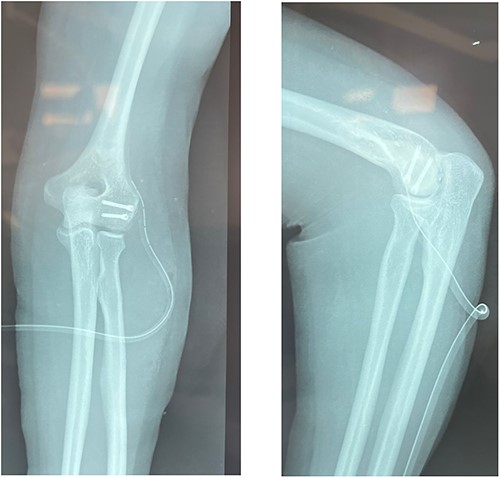

In a supine position, under regional anesthesia and with an upper limb tourniquet, the fracture was approached through a lateral Kocher approach. After exposing the capitulum, the fracture site was cleared of any hematoma or loose pieces of bone. Inspection of the joint found no intraarticular extension of the fracture. Temporary fixation was obtained by using two guide wires for the cannulated headless screws and checked with image intensification. The position of the wire should be as perpendicular as possible to the fracture line. After anterior to posterior drilling, Herbert screws were inserted. A last check for fracture stability under visual inspection (Fig. 3) as well as under image intensification was done (Fig. 4).